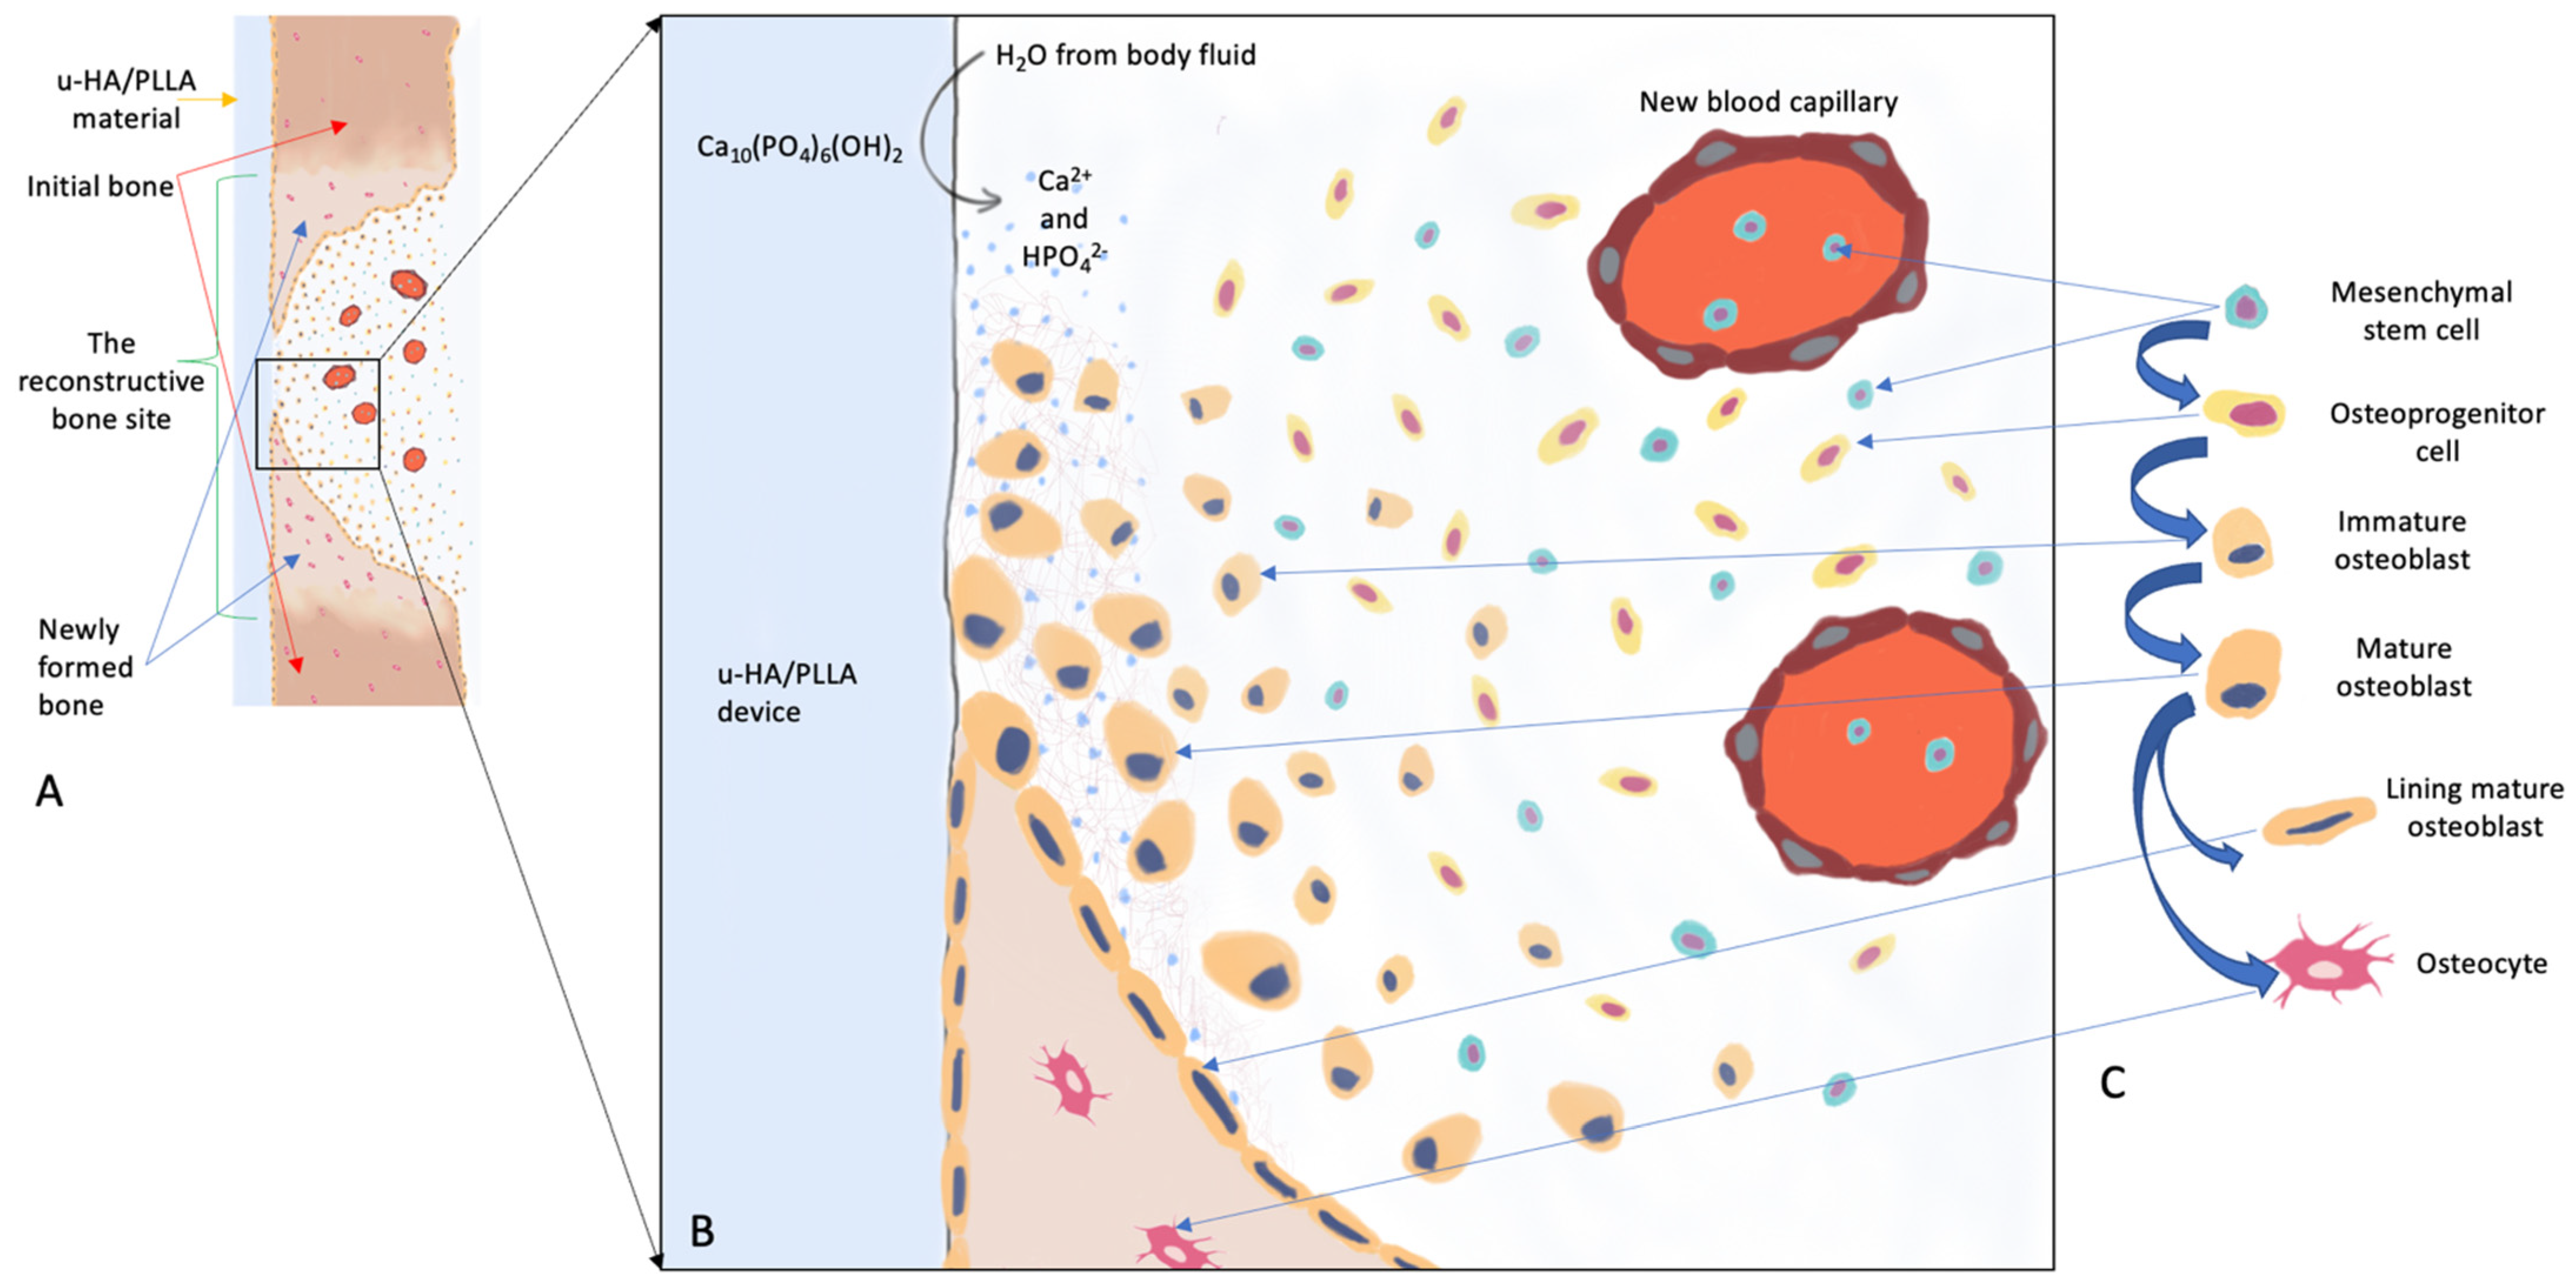

2. u-HA/PLLA, an Outstanding Bioresorbable Composite

2.1. Uncalcined and Unsintered Hydroxyapatite

2.2. PLA (PLLA, PDLA, PDLLA)

2.3. Forged Composite of u-HA Particles and PLLA Polymer